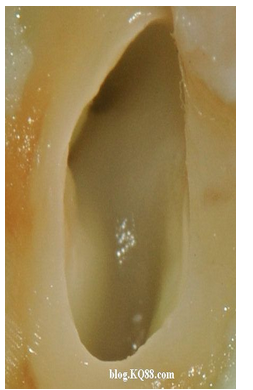

換用5%左右的次氯酸鈉很快髓腔內(nèi)的牙髓溶解了

單靠次氯酸鈉作用后的髓腔